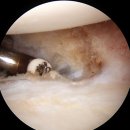

검지, 중지 세 손가락이 저려서 잠도 못 주무신다고 하여 물리치료, 침치료 등을 하셨다. 그래도 호전되지 않아서 수술을 고민하다가 천안 불당에 있는 서울대정병원에 가게 되었다. 주차는 지하1층에서 지하3층까지이다. 주차 요금을 받는다는 안내문 때문인지 주차가 어렵지는 않았다. 수술 환자는 주차요금을 따로...

. 안녕하세요 이선이 아빠입니다.👋🖐👋🖐 . 오늘은 천안 불당동 서울대정병원 수술후기입니다. (현재도 진행중😭😭) . 서울대정병원 : 네이버 방문자리뷰 1,011 · 블로그리뷰 347 naver.me ⏰️운영시간 월화수목금 09:00 ~ 21:00 토일 09:00 ~ 16:00 ☎️전화번호 041-415-0001 🚗주차 지하주차장과 지상주차장이 있습니다...

사람이 있다고는 하지만 자식 입장에서는 크다면 큰 수술이다보니 좀 더 여러 후기를 찾아보고 싶었지만 딱히 나오는 글은 없었다(그래서 이 글을 쓰는 계기이기...원장님을 믿고 수술을 진행하고 싶다고 했고, 의사를 존중했기에 서울대정병원에서 인공관절 반치환술을 진행했다. 수술 과정 수술 결정 전, MRI 촬영을...